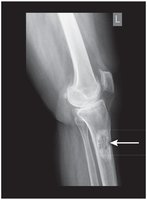

Dislocation and Arthritis

Dislocation: Complete displacement of a bone from its joint.

Osteoarthritis: Degenerative joint disease, bones in direct contact.